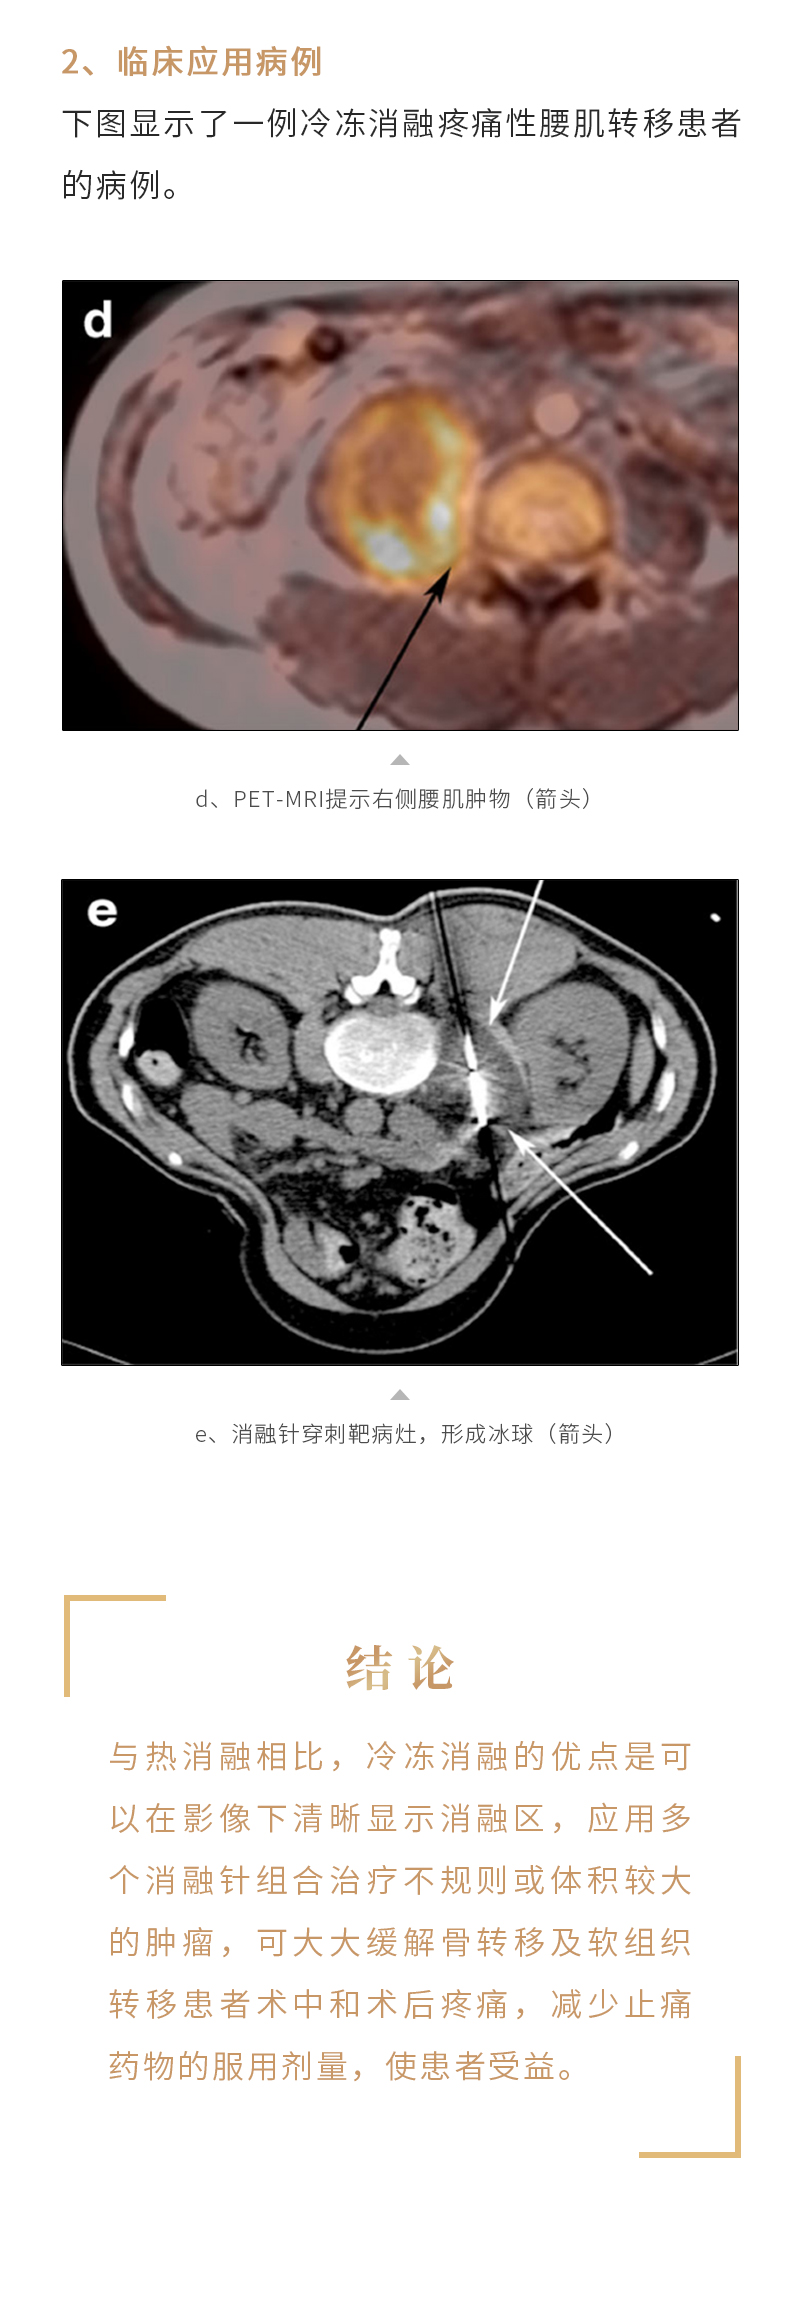

冷凍消融治療骨與軟組織腫瘤——【海杰亞科研資訊】第243期